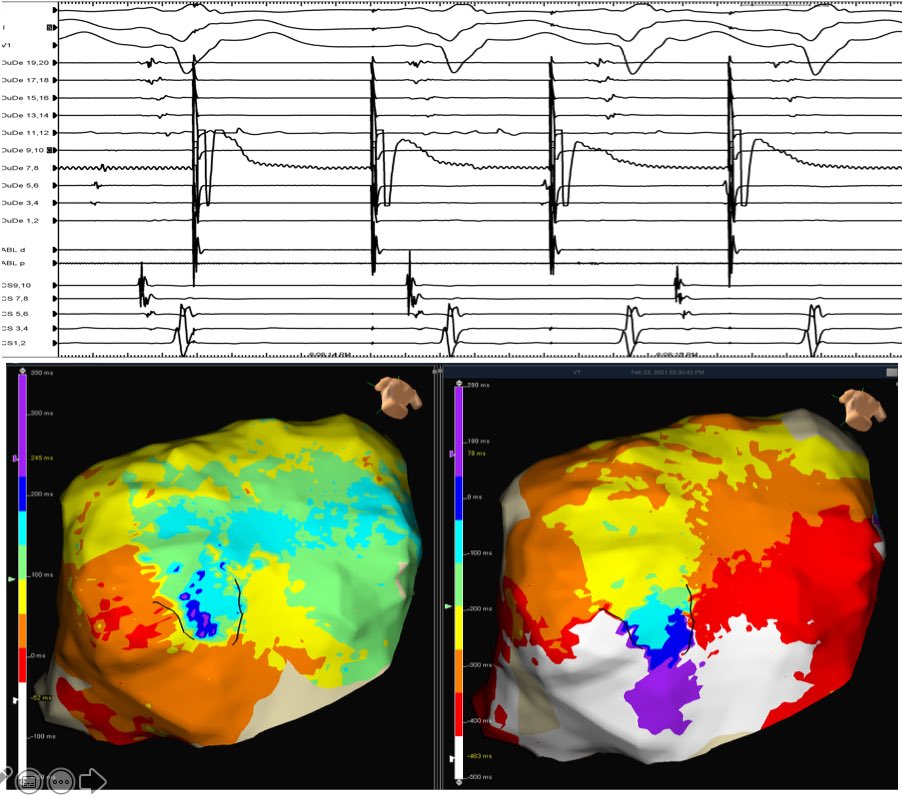

Map by @Noozie2

Amazing case (1:38h) endo/epi VT ablation (2 prior failed endocardial ablations at OSH). Great epicardial circuit and nice example of Non-propagated stimulus @DrRoderickTung